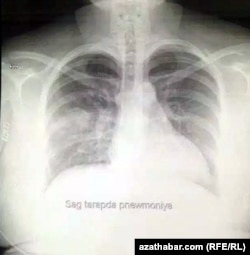

Рентгеновский снимок легких пациента с COVID-19

Также редакция Радио Азатлык получила рентгеновские снимки пациентов, заразившихся COVID-19.